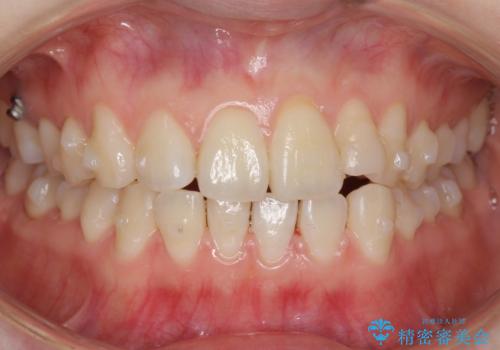

歯を大きくかぶせるスペースを作るため、右上の奥歯を後ろに下げています。

矯正用ミニスクリューを1本、使用しています。

左にずれていた上の正中も揃い、大変喜んでいただきました。